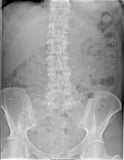

The principle is that the patient swallows a fix dose of Transit-Pellets™ radiopaque markers for six days. On day seven, a single abdominal radiograph is taken. The patient colonic transit time is calculated as the mean oro-anal transit time (OATT, mouth-to-anus) in days of swallowed doses. This value is obtained base on the number of retained markers that are left and in which segment the markers are located.

This is the World’s Premiere web base A.I System for colonic transit study under the name of Transit-Pellets™ GI Monitoring System. The system can be used in real-time using any device connected to the Internet and is available to all healthcare practitioner account holders. With GI Monitoring system, the user is able to follow a step-by-step guide, enters the number and location of markers as shown in the patient’s x-ray.

The system automatically then calculates the patient total and segmental colonic transit time according to Transit-Pelletsmethod™. The report displayed after each test shows the patient colonic test results in both graphical and report format benchmarked against Transit-Pelletsmethod™ proprietary reference values.